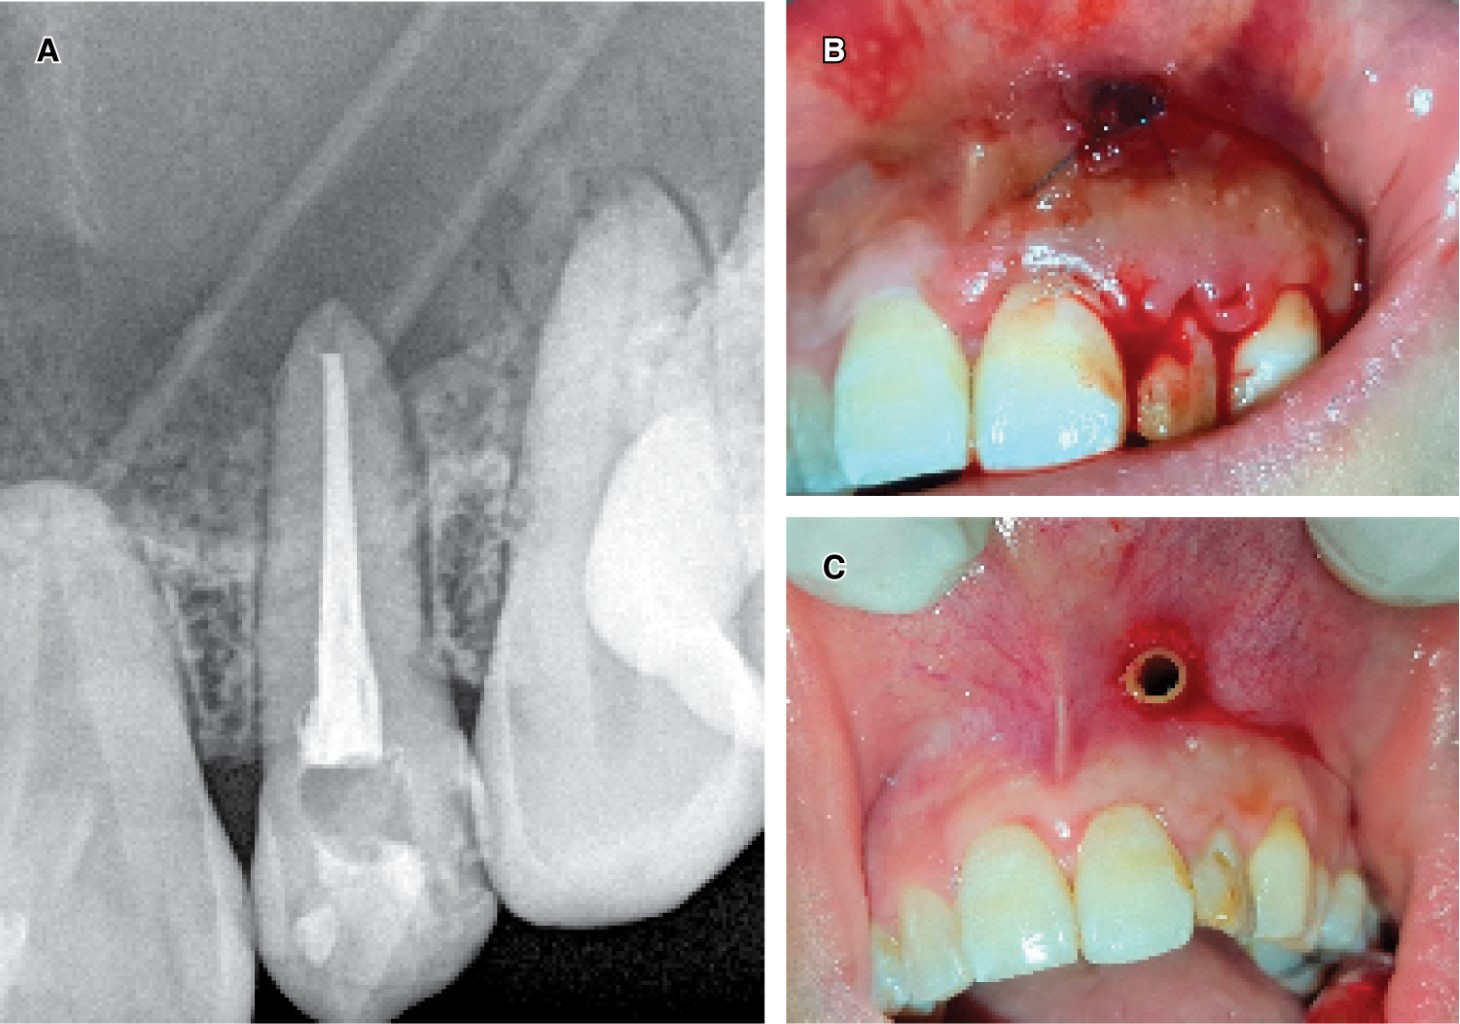

The intraoral examination revealed a slightly enlarged area in the palatal fibromucosa lateralized to the left, fluctuating, with a tendency to suppuration and pain on palpation. The provisional diagnosis was a palatal abscess, showing the upper right lateral incisor with a grayish coloration, negative pulp excitability test, and clinical suspicion of pulp necrosis. X-ray (periapical technique) showed a large radiolucent lesion in the cortex that extended beyond the areas confined to the problematic tooth (Figure 1).

In addition, as a relevant radiographic finding, a zone of radiodensity similar to dentin was observed at the level of the enamel-cementum junction, associated with an invagination of dental tissue circumscribed by a radiopaque area, compatible with DI.

• 1) Treatment of the involved tooth and lesion diagnosis phase: with radiographic and tomographic images, after treatment with antibiotics and having drained the palatal lesion, the root canal treatment of the involved tooth was done, and with rotatory instruments was eliminated the DI, both situations without inconvenience. Due to the endodontic-surgery inter-discipline, endodontic therapy was applied in two sessions, with an intermediate calcium hydroxide-based therapy. An expectant behavior was kept regarding the remaining dental elements compromised with the infectious. An incisional biopsy of the intraosseous lesion was immediately indicated. For this, a mucoperiosteal flap was made from the anterosuperior sector, trepanning, and preserving the vestibular cortex, incising 4 mm from the apex of the compromised tooth. An extensive bone cavity with liquid content was identified, covered by a capsule of difficult enucleation, which was partially extracted for histopathological study. Subsequently, the flap was replaced and sutured together with the placement of a silicone tube for decompressive purposes. The histopathological result revealed a maxillary inflammatory cyst. Figure 3A and 3B show the X-ray image of the drainage through which the patient flushed the cystic cavity. Figure 3C the tissue surrounding the catheter is normal in appearance. This photo was taken four months after initial placement during a device replacement procedure.